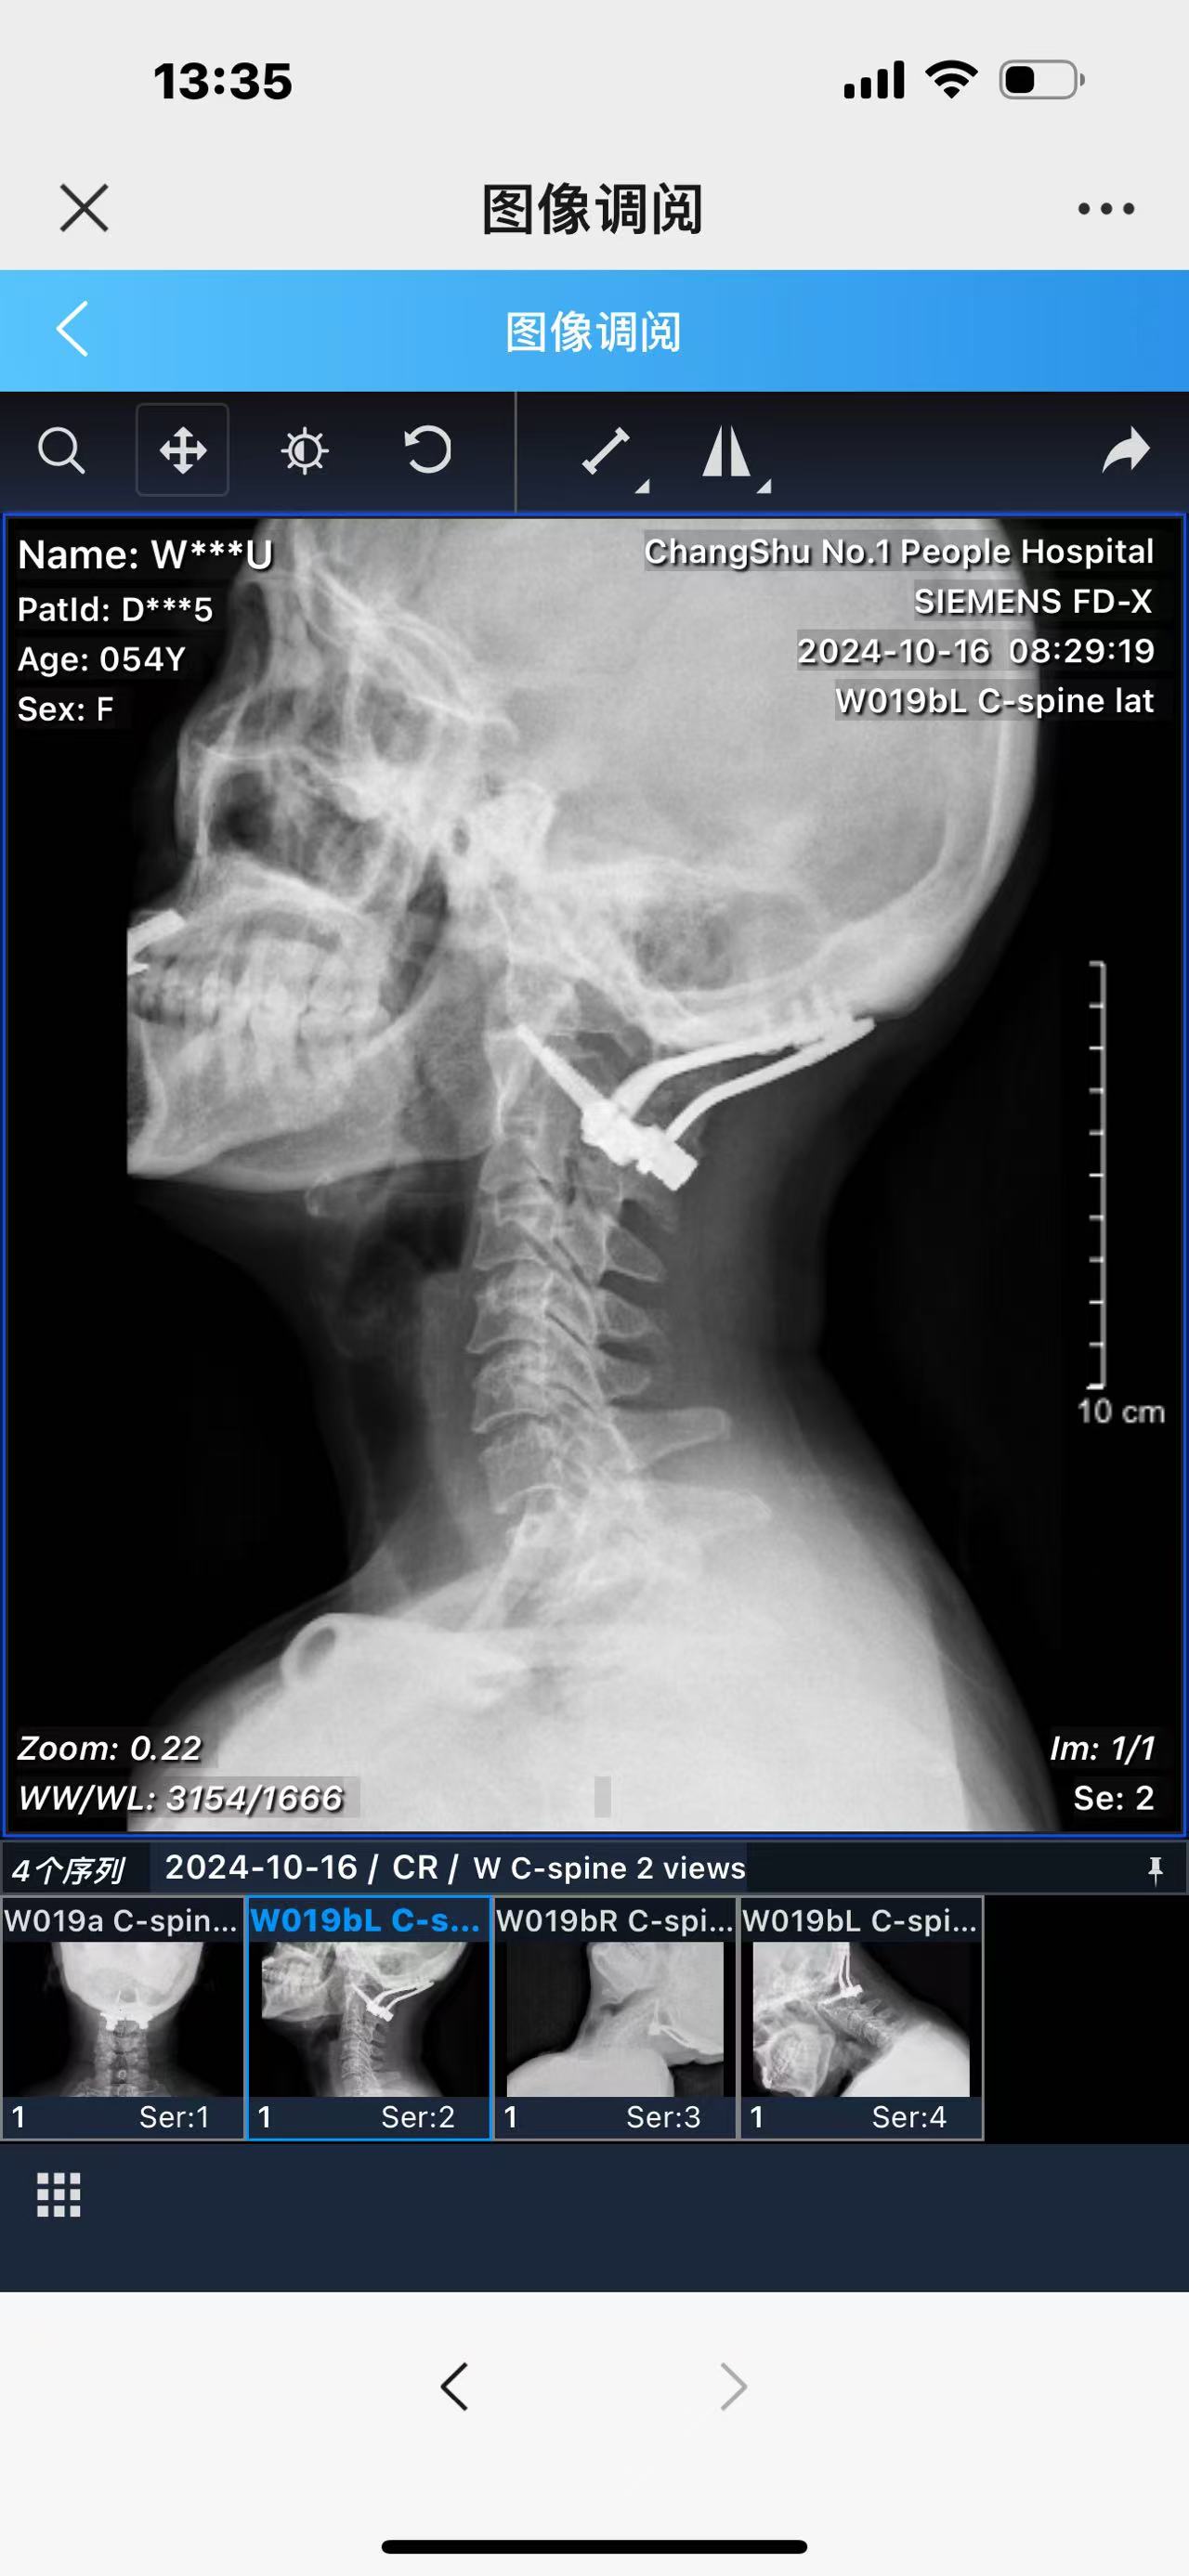

• 术后影像: